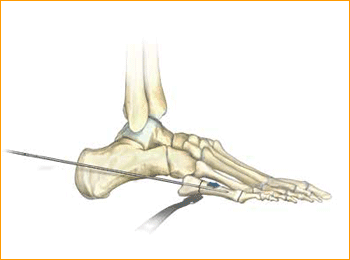

Jones Fracture Technique for 4.5 mm and 5.5 mm Headless Compression screws.

1. PATIENT POSITIONING

Position the patient in a semi-lateral position utilizing a bean bag body positioner. The patient should be moved to the distal end of the bed and the operative leg draped free as the side up. Exertion of the operative limb should be checked prior to prep and drape to confirm that

the operative limb can be positioned on the mini c-arm during surgery.

2. INDICATION AREA OUTLINE

The base of the fifth metatarsal is outlined, including the insertions of the peroneus brevis and tertius tendons.

3. APPROACH AND EXPOSURE

The guide wire, .062″, for the 4.7 Screw can be positioned at the base of the fifth metatarsal under fluoroscopic guidance. A small incision is made at the base of the fifth metatarsal at the intersection of the peroneus brevis and tertius tendons. Care is made to identify and protect the sural nerve branches which run over the peroneal tendons. If necessary, fibers of the lateral aponeurosis and peroneus brevis tendon are separated and retracted away from the styloid process of the base of the fifth metatarsal. A mini Hohman Retractor is placed on the plantar

aspect of the base of the fifth metatarsal. The surgeon’s fingers can be used to reduce the fifth metatarsal fracture by placing them in between the fourth and fifth metatarsals. This closes down the fifth metatarsal fracture site during guide wire, drill, and screw placement. A guide wire is drilled from the base of the fifth metatarsal into the central portion of the metatarsal shaft. It is maintained within the intramedullary canal in order to avoid distal penetration. Confirm placement with fluoroscopy.

4. MEASURE DEPTH

Depth is measured from the exposed portion of the guide wire with the cannulated depth gauge.

5. ADVANCE GUIDE WIRE

After selecting the size, advance the guide wire approximately 5 mm to maintain distal pin fixation before drilling.

Caution: Make sure not to compromise distal joint surfaces when advancing the guide wire.

6. SOFT TISSUE GUIDE PLACEMENT

Place the soft tissue guide (the guide should be used throughout) over the guide wire and open the near cortex using the appropriate cannulated profile drill.

7. DRILL

Leaving the soft tissue guide in place, drill into the far fragment with the appropriate cannulated, long drill. Reference the markings on the drill to confirm desired depth.

Tip: The long drill is recommended to mitigate the effects of varying bone density and distraction upon screw insertion.

8. FRACTURE COMPRESSION

In order to account for countersinking and fracture compression, a screw that measures 5 mm shorter than the measured total depth is inserted over the guide wire while protecting the soft tissues with a soft tissue guide.

9. SCREW INSERTION

The screw is placed while under fluoroscopic guidance in order to avoid cortical penetration. Postoperative protocol: The patient is placed into a soft dressing, supported by a fiberglass splint. Patients can be made non-weight-bearing for a period of 2–6 weeks postoperatively depending upon Torg type of fracture, bone quality, and underlying morbidities.